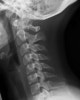

- 허리나 목이 아픈 환자가 X-ray를 찍고 나서 "뼈에는 이상이 없고 디스크 끼가 좀 보이네요."라는 말을 자주 듣게 됩니다.

디스크 역시 마찬가지로 X-ray에서는 볼 수 없습니다.

디스크의 상태를 감별하기 위해서는 MRI를 촬영해야 합니다.

'디스크 끼'라는 용어는 의학용어가 아니라 환자에게 쉽게 설명하기 위한 용어입니다.

하지만 '디스크 끼'라는 말이 너무 공공연하게 쓰이고 있어 이 자체도 환자들에게 혼란을 주고 있습니다.

X-ray를 찍고 '디스크 끼'가 보인다는 말의 의미는 척추뼈와 척추뼈 사이의 간격이 좁다는 의미가 입니다.

척추뼈 사이에 디스크가 위치하고 있기 때문에 사이의 간격이 좁으면 디스크가 눌렸다고 추정하는 것이죠.

하지만 이것은 정확한 진단이 아니라 부정확한 추정에 불과합니다.

환자가 진짜로 디스크 증상을 보이고 있는 환자라면 MRI를 찍는 것이 마땅합니다.

그것이 아니라면 X-ray만으로 디스크 진단을 하고 그 진단에 따라 치료를 하는 것은 잘못된 것입니다.

X-ray 대신 면밀한 이학적 검진을 통해 목과 허리 통증의 원인을 더 잘 찾을 수 있습니다.